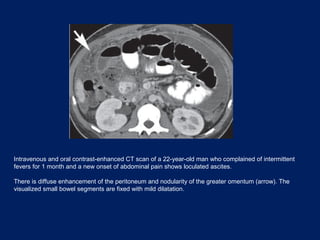

Intravenous and oral contrast-enhanced CT scan of a 22-year-old man who complained of intermittent

fevers for 1 month and a new onset of abdominal pain shows loculated ascites.

There is diffuse enhancement of the peritoneum and nodularity of the greater omentum (arrow). The

visualized small bowel segments are fixed with mild dilatation.